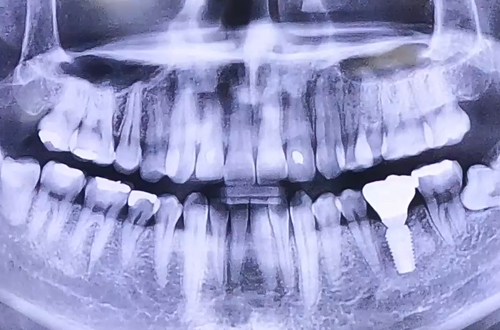

BEFORE

AFTER

치료 유형 뼈이식 임플란트